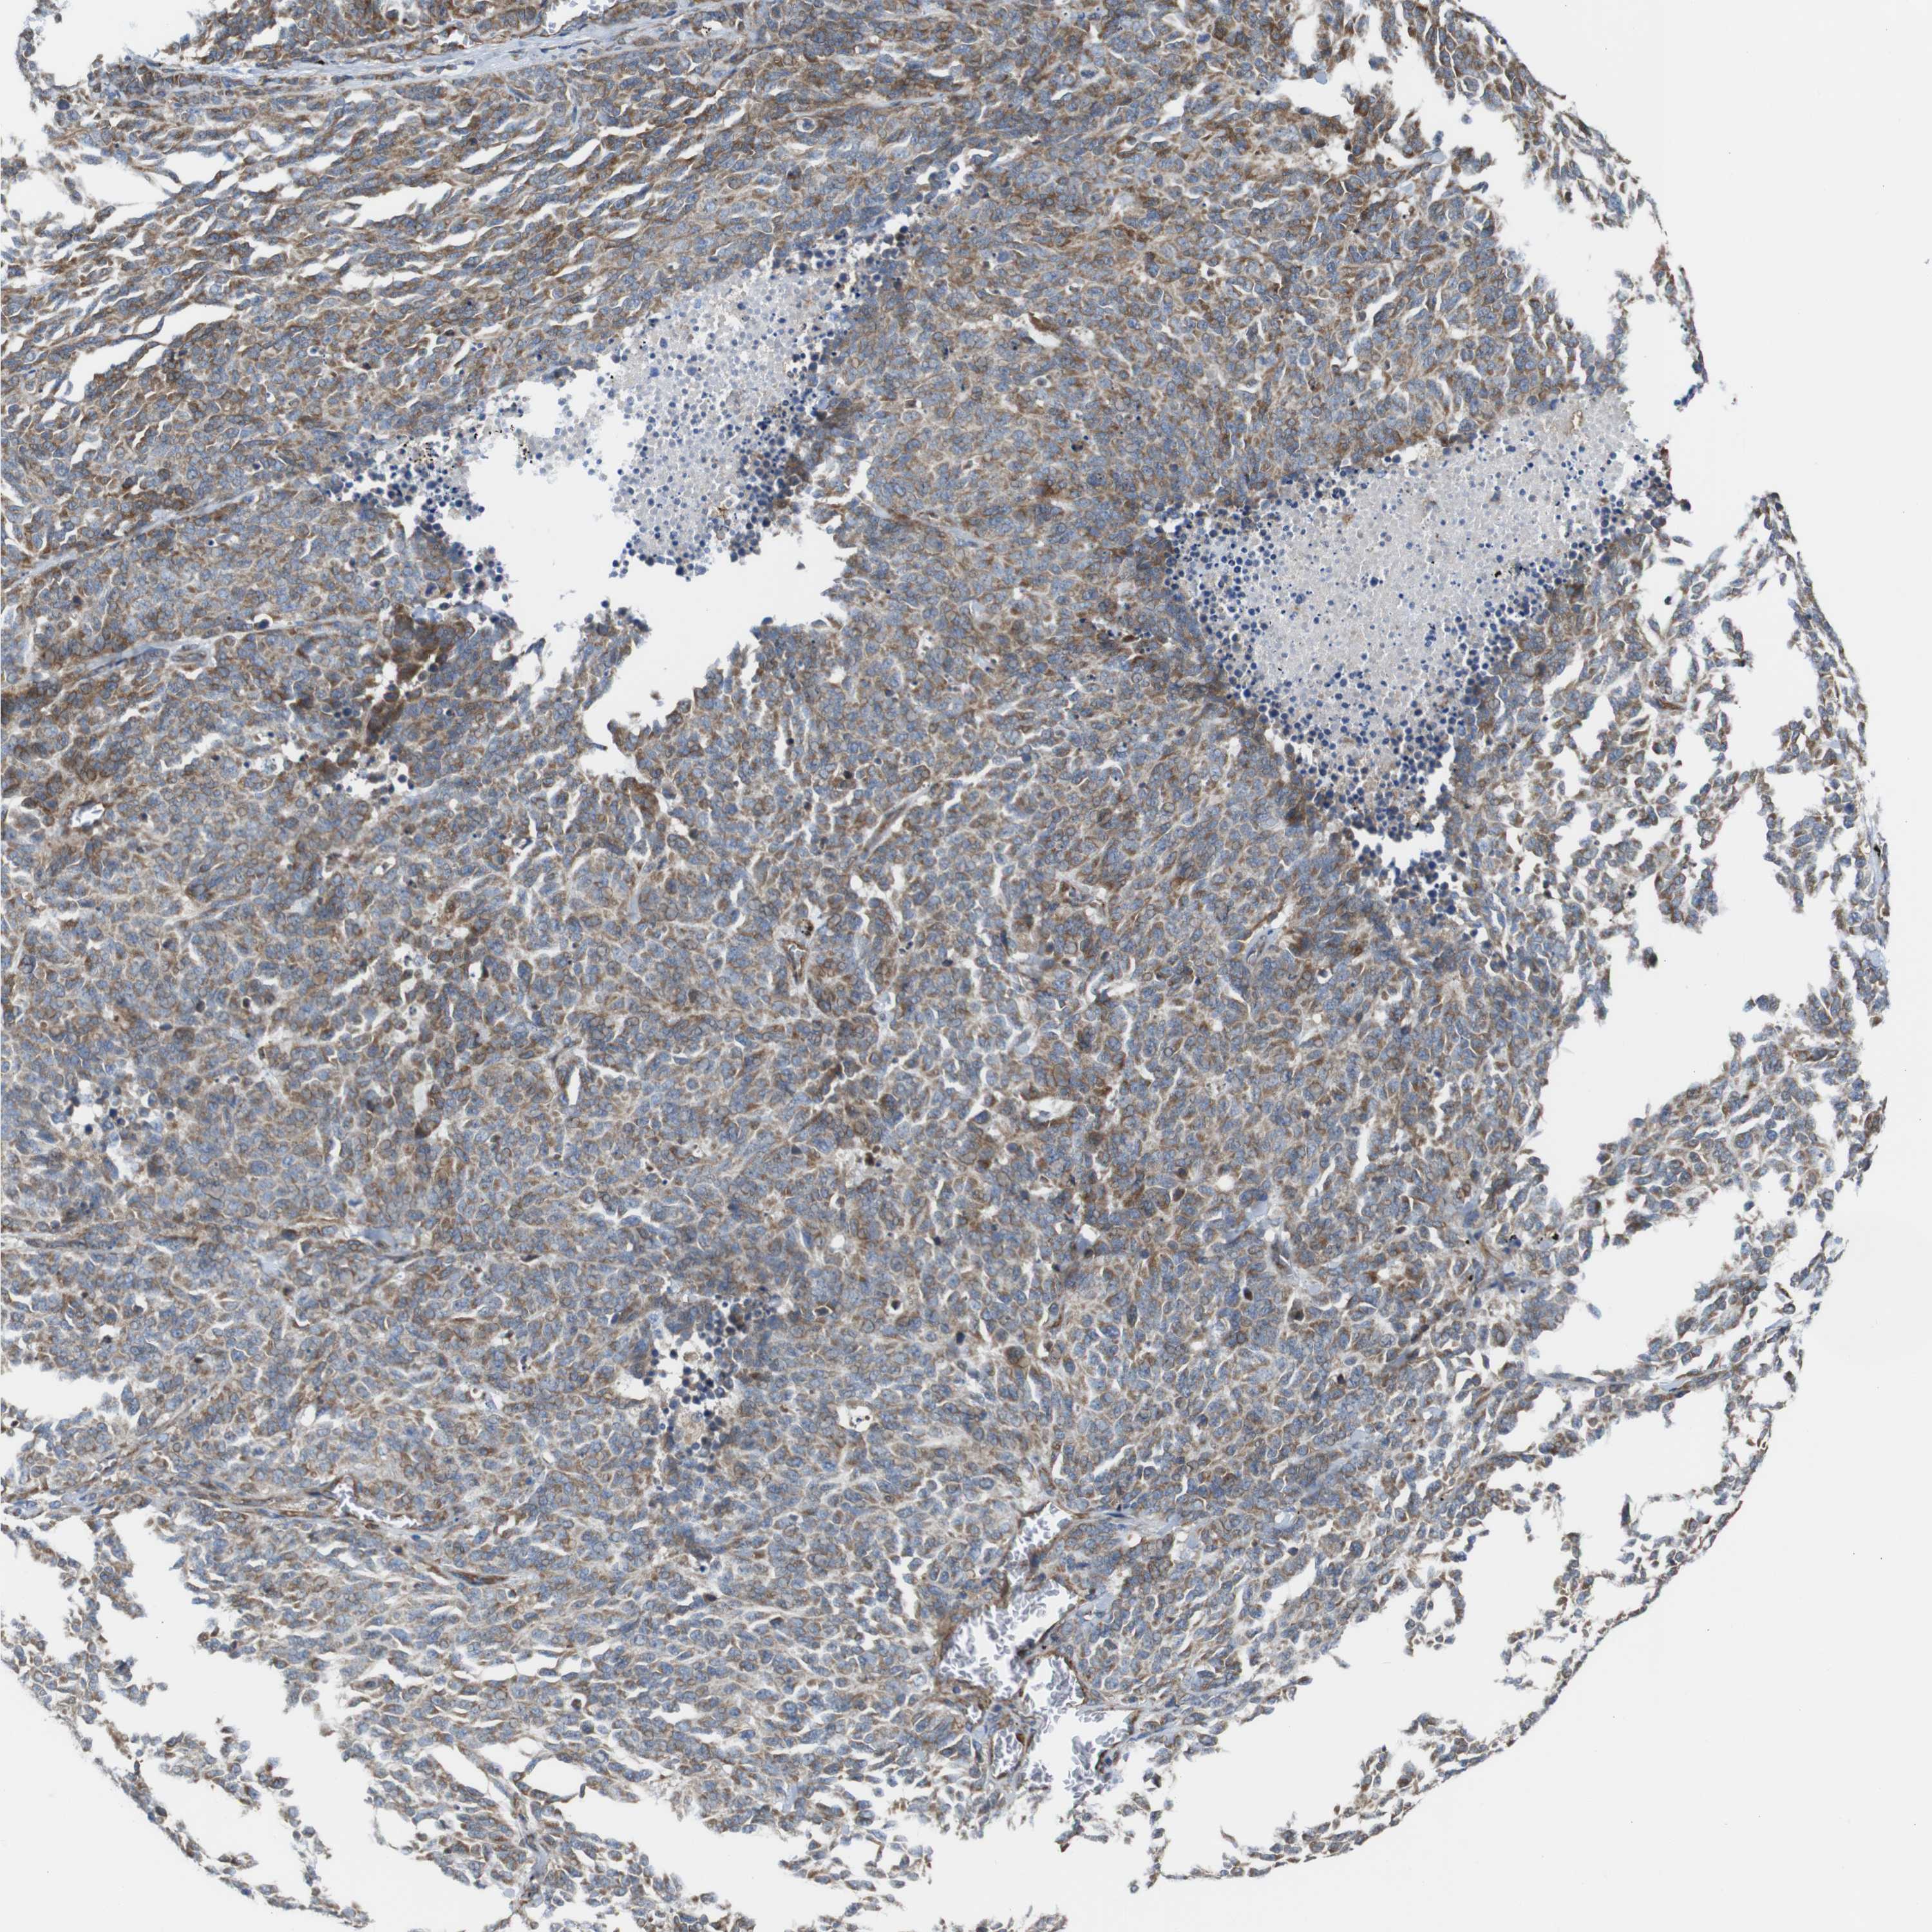

CANCER LUNG CANCER Show tissue menu

Lung cancer

Human cancer